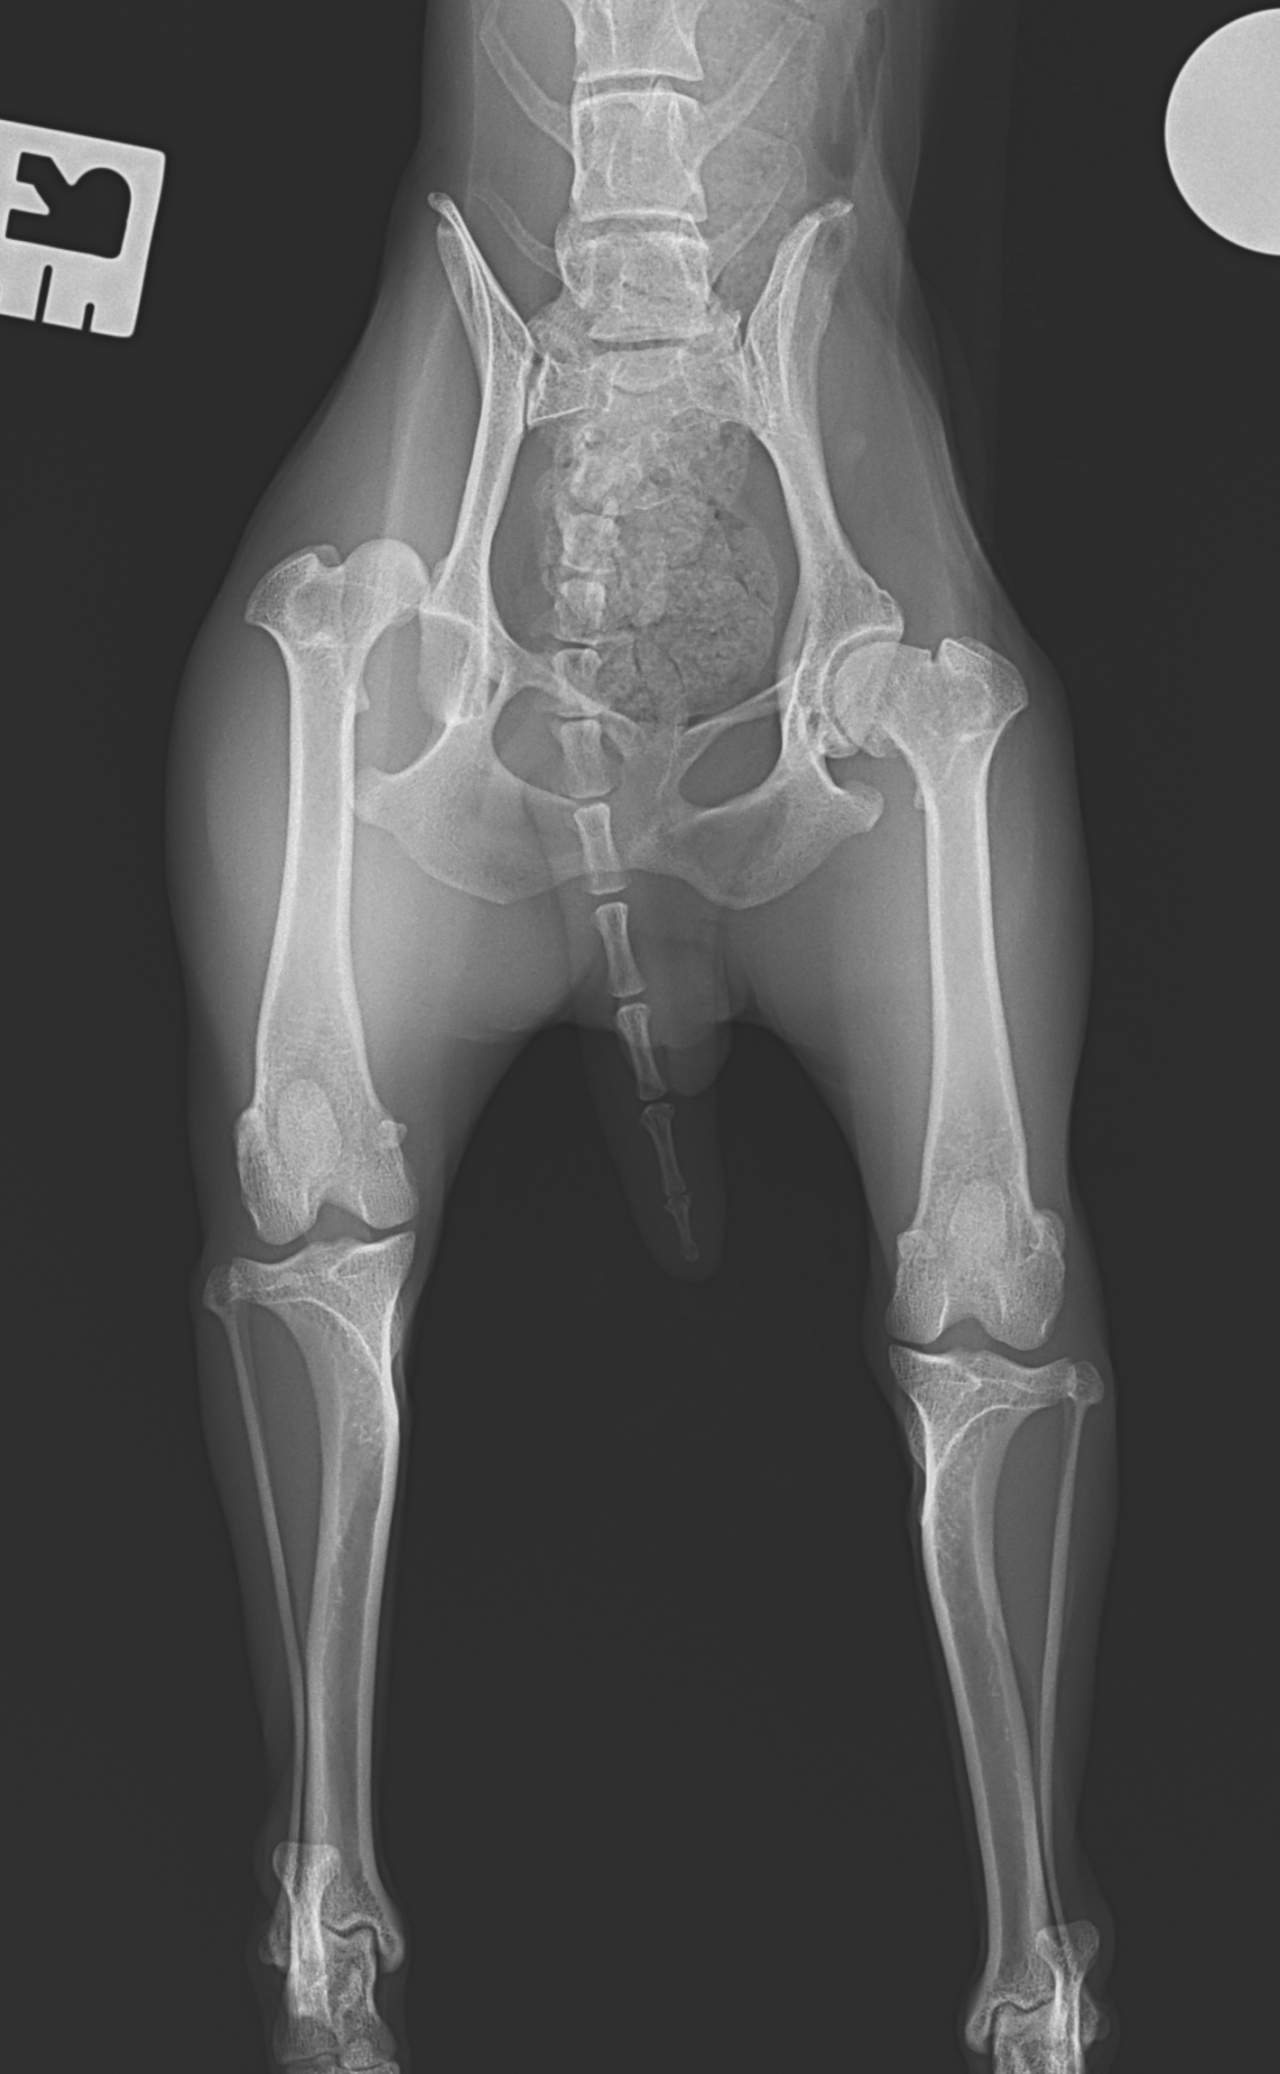

股関節脱臼に対するトグルロッド #62

トイ・プードルが室内で転倒し、股関節脱臼を起こしたとのこと。失われた股関節機能を取り戻すために、大腿骨頭靭帯をもっとも生理的な方法で再建する”Toggle Rod法”で対応しました。シンプルかつ短時間で施術が可能です。外側アプローチ、寛骨臼にφ2.5の骨孔を形成。2.4砲弾型トグルロッドにポリエステル縫合糸を装着し、寛骨臼内の骨孔に刺入する。大腿骨頭側より骨頭靭帯付着部位から第3転子に向け2.0のボーントンネルを作成。第3転子側よりパッサーでスーチャーリレーし、エンドボタンで第3転子に締結。”適応症例の選択さえ間違えなければ、誰がやっても成功率の高い治療成績が担保されている”。そういった術式こそ本当に必要とされる術式です。しかしながら、再脱臼(20%)は2週間以内に起こることが知られているので、術後しばらくは安静が必要です。